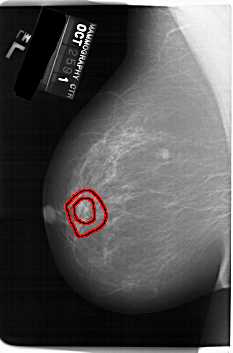

A_1253_1.LEFT_CC

LEFT_CC LINES 6691 PIXELS_PER_LINE 4141 BITS_PER_PIXEL 12 RESOLUTION 43.5 OVERLAY

FILE: A_1253_1.LEFT_CC.OVERLAY

TOTAL_ABNORMALITIES 1

ABNORMALITY 1

LESION_TYPE MASS SHAPE IRREGULAR MARGINS ILL_DEFINED

ASSESSMENT 4

SUBTLETY 2

PATHOLOGY MALIGNANT

TOTAL_OUTLINES 2

BOUNDARY

CORE